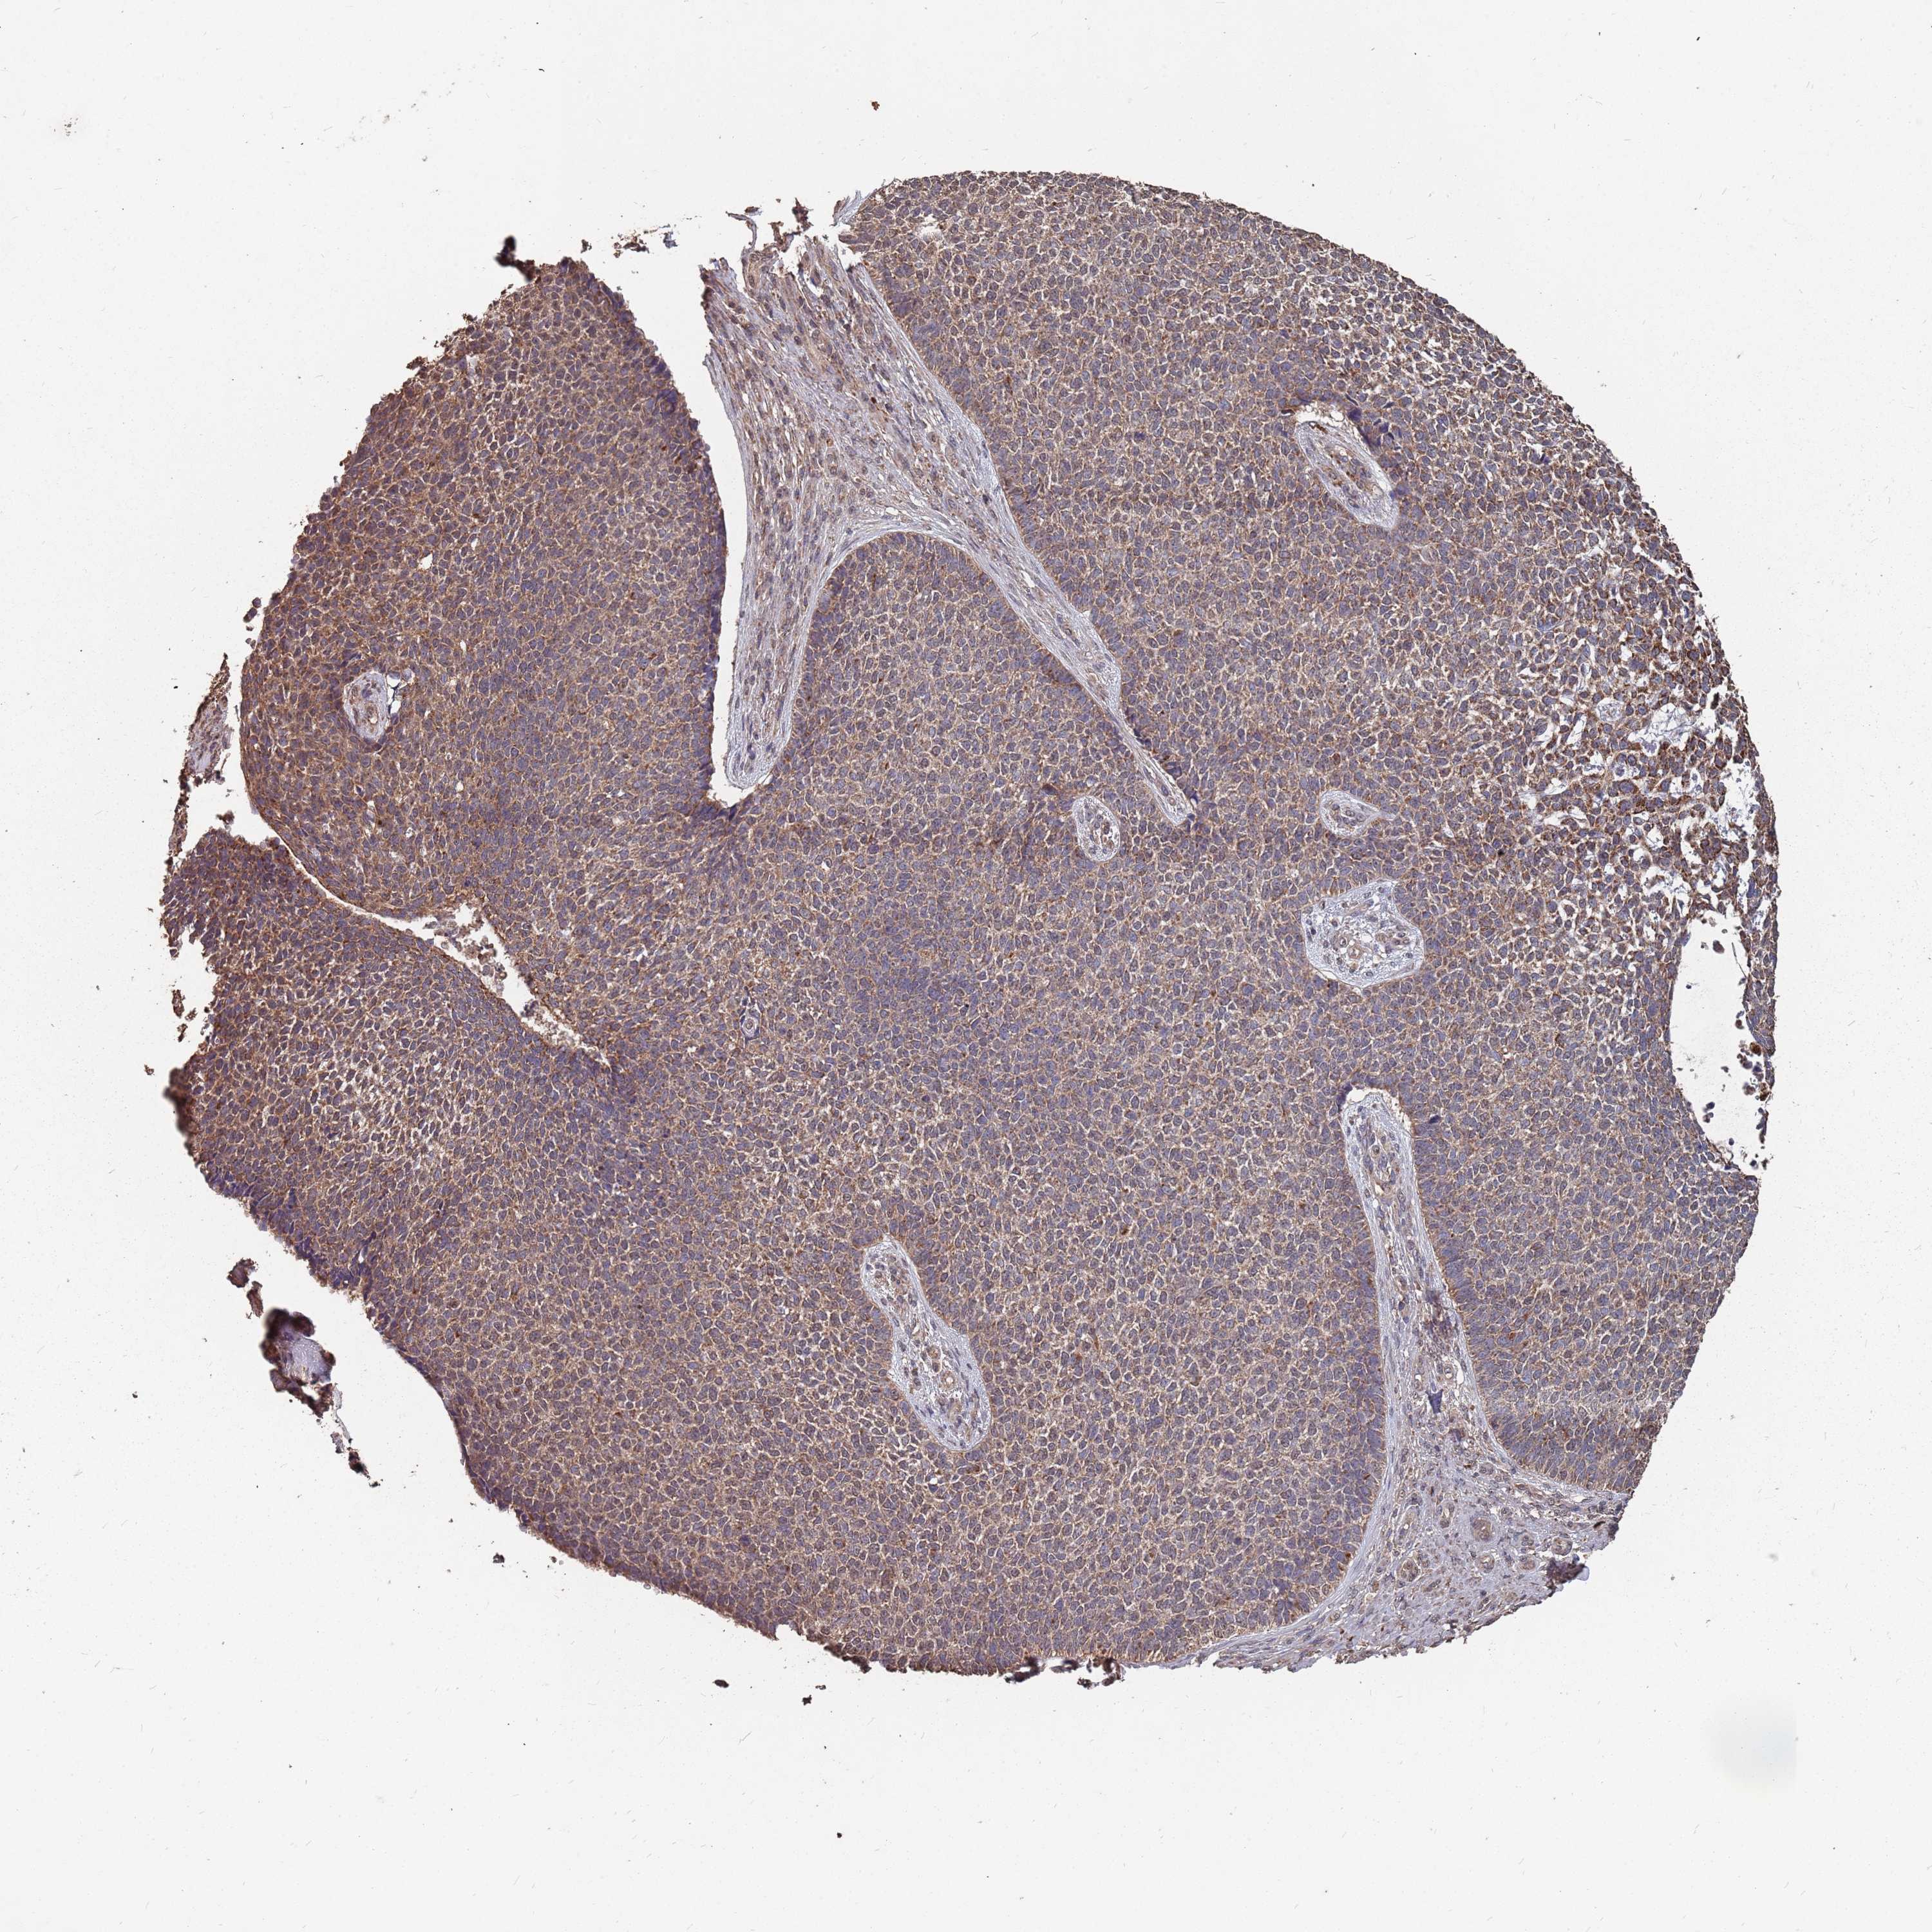

SKIN CANCER - Protein expressioni

A mouse-over function shows sample information and annotation data. Click on an image to view it in a full screen mode. Samples can be filtered based on level of antibody staining by selecting one or several of the following categories: high, medium, low and not detected. The assay and annotation is described here.

Antibody stainingi

Antibody staining in the annotated cell types in the current human tissue is reported as not detected, low, medium, or high, based on conventional immunohistochemistry profiling in selected tissues. This score is based on the combination of the staining intensity and fraction of stained cells.

Each image is clickable and will lead to virtual microscopy that enables deeper exploration of all samples and also displays staining intensity scores, fraction scores and subcellular localization as well as patient and tissue information for each sample.

Antibody HPA020459

Basal cell carcinoma

Squamous cell carcinoma, NOS

Squamous cell carcinoma, metastatic, NOS